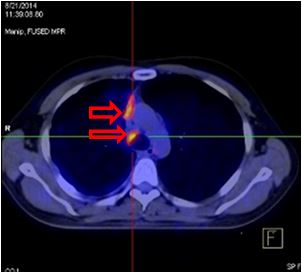

Hình ảnh PET/CT sau 3 đợt điều trị duy trì với Pemetrexed: các khối di căn và hạch không phát triển, max SUV có xu hướng giảm.

Nhiều nốt mờ dải rác phổi phải, màng phổi, max SUV = 4,25. Hạch cạnh khí quản 1,5 cm, max SUV = 4,93 (đầu mũi tên đỏ)

Hình ảnh PET/CT sau 3 đợt điều trị duy trì với Pemetrexed: các khối di căn và hạch không phát triển, max SUV có xu hướng giảm.Hình ảnh PET/CT sau 8 đợt hóa chất: nhiều nốt mờ dải rác phổi phải, màng phổi, max SUV = 4,7. Hạch cạnh khí quản 1,5 cm, max SUV = 6,4